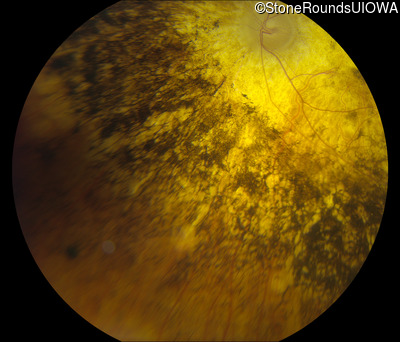

Fundus Photography - Left - Light Perception

Exemplar

Fundus Montage - Left - Light Perception